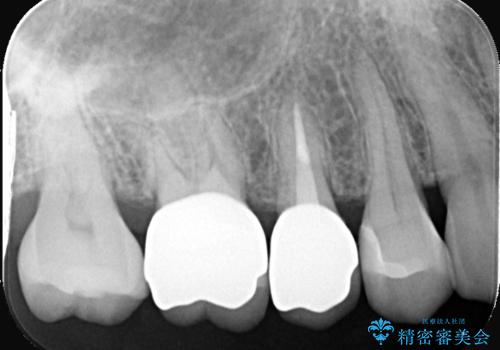

虫歯治療後は、形やかみ合わせを細かく調整しながら、セラミッククラウンを作製・装着しました。金属を使わないセラミックは見た目が自然なだけでなく、適合性も高いため、再びむし歯になるリスクを抑えることができます。

治療後は、見た目の改善だけでなく、咬み心地や違和感の改善にもつながり、患者さんからは「しっかり噛めるようになって安心した」との声をいただきました。